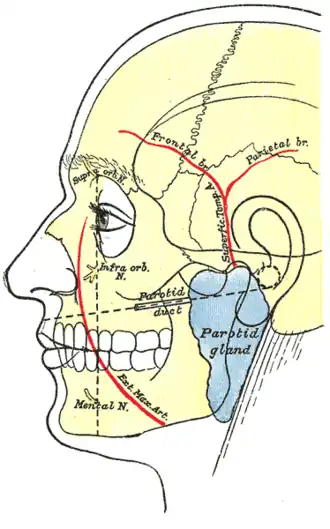

Outline of side of face, showing chief surface markings.

Outline of side of face, showing chief surface markings. -